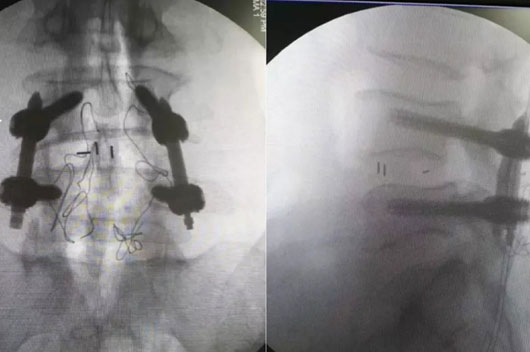

µÚÒ»²½£ºÊõÖÐÓ°Ïñ×°±¸¡ª¡ªÊõÖÐÈýάCÐͱ۶Ի¼Õß¾ÙÐÐÑü×µÓ°ÏñɨÃè¼°ÈýÎ¬ÖØÐÞ£¬£¬£¬£¬£¬£¬£¬£¬Í¼Ïñ±»Í¬²½´«ÊäÖÁ¹Ç¿ÆÊÖÊõ»úеÈËϵͳ¡£¡£¡£¡£¡£¡£¡£

µÚ¶þ²½£ºÒ½ÉúÔÚ²Ù×÷ϵͳÉÏÍýÏëºÃÂݶ¤µÄ½Ç¶È¡¢Æ«Ïò¡¢³¤¶È¼°Ö±¾¶µÈÒªº¦ÒòËØºó£¬£¬£¬£¬£¬£¬£¬£¬»úе±Û×Ô¶¯µÖ´ïÒ½ÉúÉè¼ÆµÄÀíÏëλÖᣡ£¡£¡£¡£¡£¡£

µÚÈý²½£ºÒ½ÉúÑØ×ÅÌ×Ͳ×êÈë·öÒýÕ룬£¬£¬£¬£¬£¬£¬£¬È·ÈÏλÖÃÎÞÎóºó£¬£¬£¬£¬£¬£¬£¬£¬ÔÙ°ÑÖ±¾¶6.5ºÁÃ׵ĿÕÐÄ×µ¹¸ùÂݶ¤Í¨¹ý·öÒýÕëÀο¿£¬£¬£¬£¬£¬£¬£¬£¬°Î³öµ¼Õë¡£¡£¡£¡£¡£¡£¡££¨Í¼Îª½ËÕÊ¡ÈËÃñÒ½Ôº¼¹ÖùÍâ¿ÆÖ÷ÈÎÒó¹úÓ½ÌÊÚÖÃÈë·öÒýÕë¡¢Öö¤£©

µÚËIJ½£ºÒ½Éú¶Ô»¼ÕßÔٴξÙÐÐɨÃ裬£¬£¬£¬£¬£¬£¬£¬È·ÈÏÂݶ¤µÄ¾«×¼Ò»Ö¡£¡£¡£¡£¡£¡£¡£